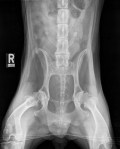

Latérale droite crâniale